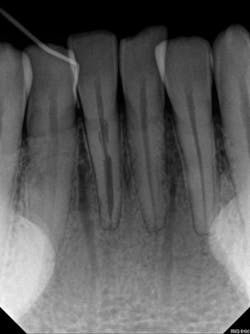

Another type of case is often encountered in practice, and that is failed RCTs. It is often unclear why an RCT fails. Small FOV CBCT images of these teeth are very revealing. Periapical lesions previously invisible on 2-D radiographs are easy to see and measure, and cracks or missed canals are also clearly visible. In this case, RCT No. 14 had been performed several years earlier. The patient said it never felt right and was now getting worse. The PA revealed nothing (PA endo). A CBCT was taken of the area and revealed a lesion on the mesiobuccal root. The reason seemed obvious when examining the MB root — there were two visible canals, with inadequate filling in either canal (CBCT endo).